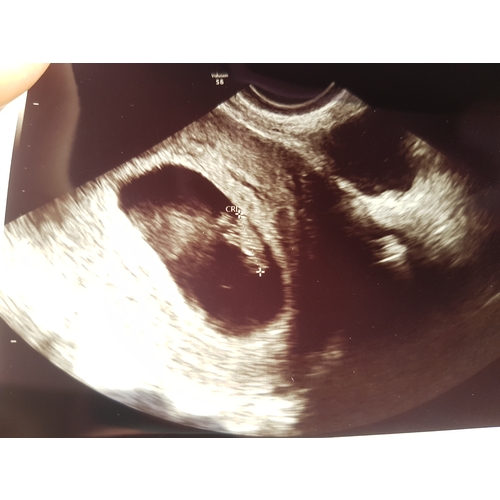

Vanmiddag bij de gynaecoloog geweest en alles was goed! Een kloppend hartje!

Het is dus mogelijk!